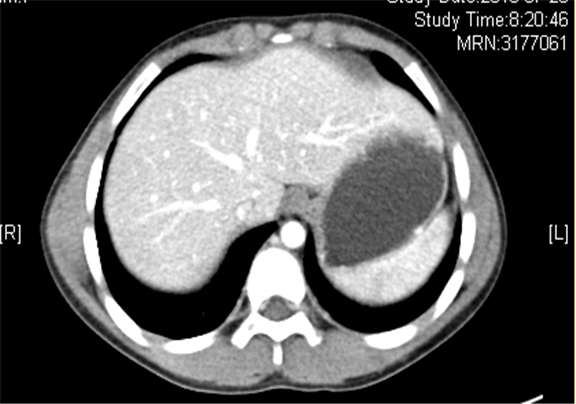

上腹部增强CT示:右侧肾上腺区占位性病变,考虑恶性肿瘤,右侧肾上腺神经母细胞瘤可能性大,请结合临床综合评价。

术前CT检查:

动脉期